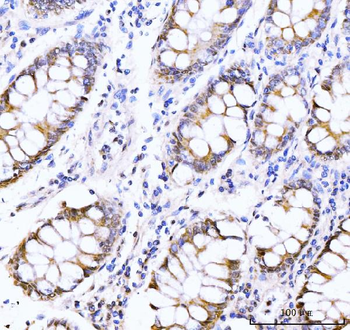

AKAP8 Antibody

| Description | AKAP8 Antibody |

| Tested applications | IHC |

| Reactivity | Human |

| Dilution range | IHC: 1/20-1/100 |